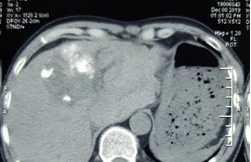

Các bác sĩ Bệnh viện Ung Bướu Hà Nội vừa thực hiện thành công ca cấp cứu u gan vỡ gây mất máu cấp, có nguy cơ tử vong cao nếu không được can thiệp kịp thời. Bệnh nhân được cầm máu bằng phương pháp nút tắc động mạch gan, giúp vượt qua “cửa tử”.

TPO - Các bác sĩ Bệnh viện hữu nghị Việt Nam - Cuba Đồng Hới vừa điều trị thành công trường hợp thứ 2 shock mất máu do u gan vỡ. Điều đặc biệt là hai bệnh nhân này đều không biết mình bị u gan.

TPO - Xác định ca bệnh cực hiếm, các bác sỹ đã tính toán kỹ lưỡng thể tích gan và dự trù các chế phẩm máu cho cuộc phẫu thuật cắt bỏ khối u gan khổng lồ.